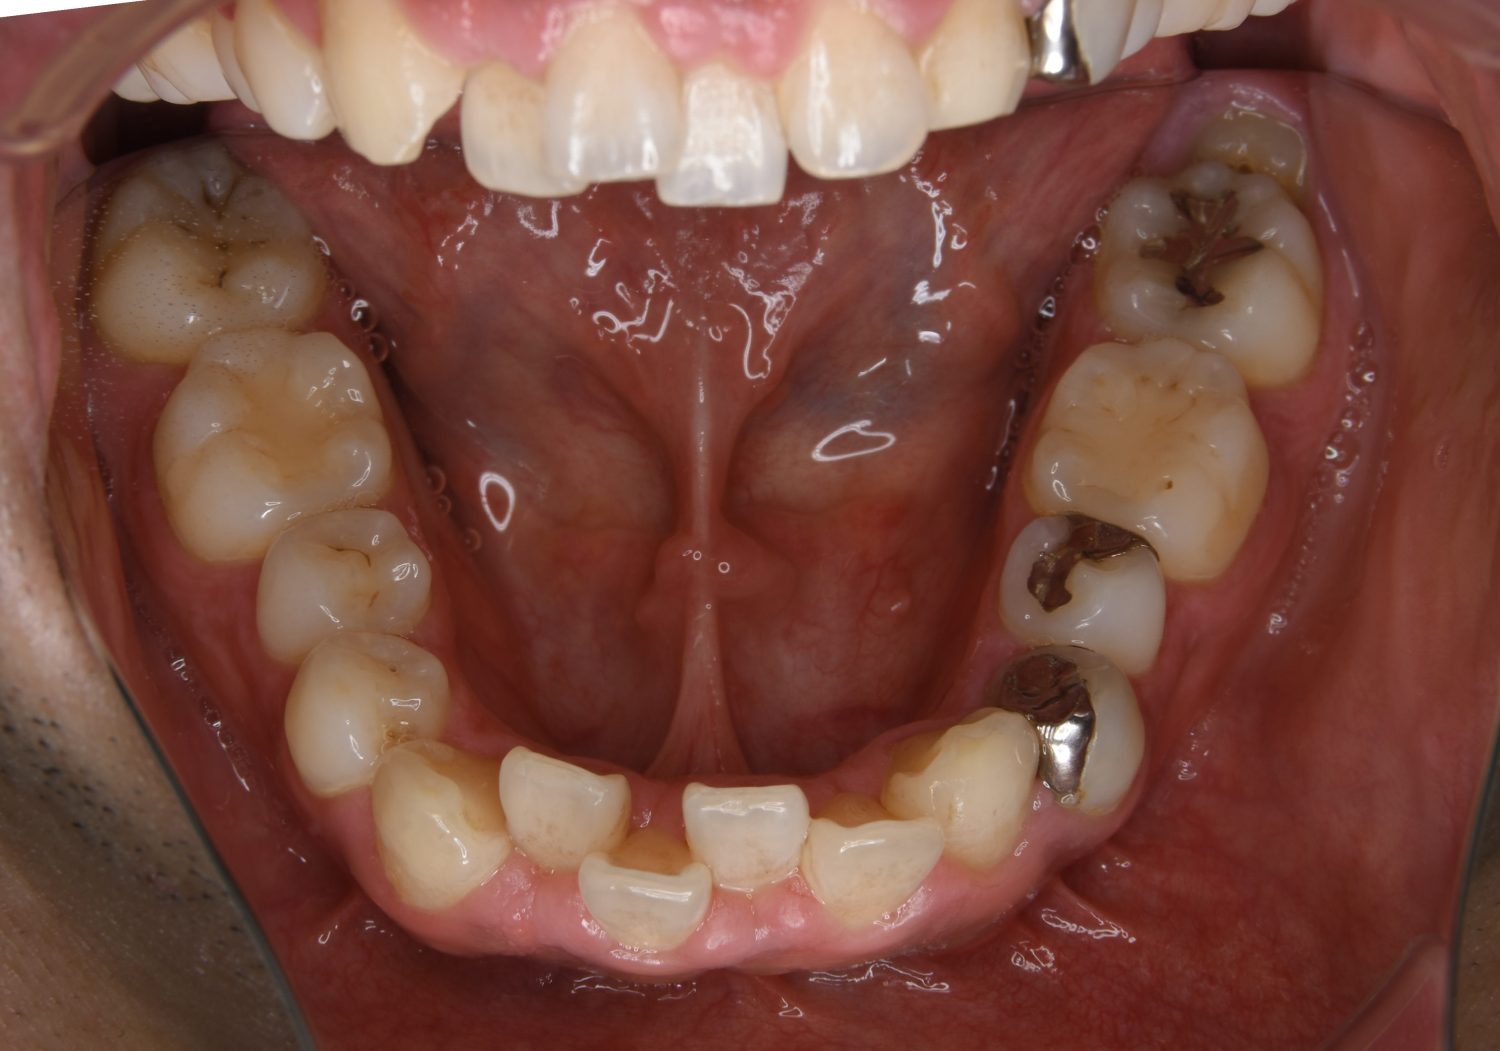

叢生の症例紹介①

Before

主訴

前歯のガタガタが気になる。

治療内容

上顎左側第一小臼歯を抜歯し、アライナー(インビザライン)にて治療を行いました。

治療費

1,150,000 円(税込)

治療期間

23ヶ月

通院回数

13回

想定されたリスク

※歯根吸収、歯肉退縮、歯髄壊死、顎関節症状

※アライナー(インビザライン)は日本の薬機法未承認の矯正装置であり、医薬品副作用被害救済制度の対象外となる場合があります。

左上の側切歯が完全に内側に入り込んでいる状態でした。左上の第一小臼歯のみ抜歯を行い治療を行うことで機能面および審美面を改善しました。